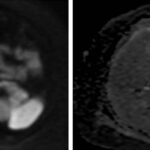

Mujer de 36 años que ingresa a Hospital Sanatorio Franchin el 11 de octubre de 2023 de forma programada para realización de duodeno pancreatectomía cefálica por tumor de cabeza de páncreas en estudio. Refiere hallazgo de lesión en forma incidental durante estudio de control hace dos meses por presentar antecedentes familiares (neoplasia endocrina múltiple). Se interna para manejo quirúrgico. Estudios de tomografía revelan formación nodular localizada en cabeza y cuerpo pancreático de paredes gruesas que mide 24 x 28 mm, que en resonancia se muestra hiperintensa en T2 y realce periférico luego de la administración de contraste endovenoso. Presenta restricción en la difusión con caída de la señal ADC, por lo que se vincula con una lesión de alta celularidad.